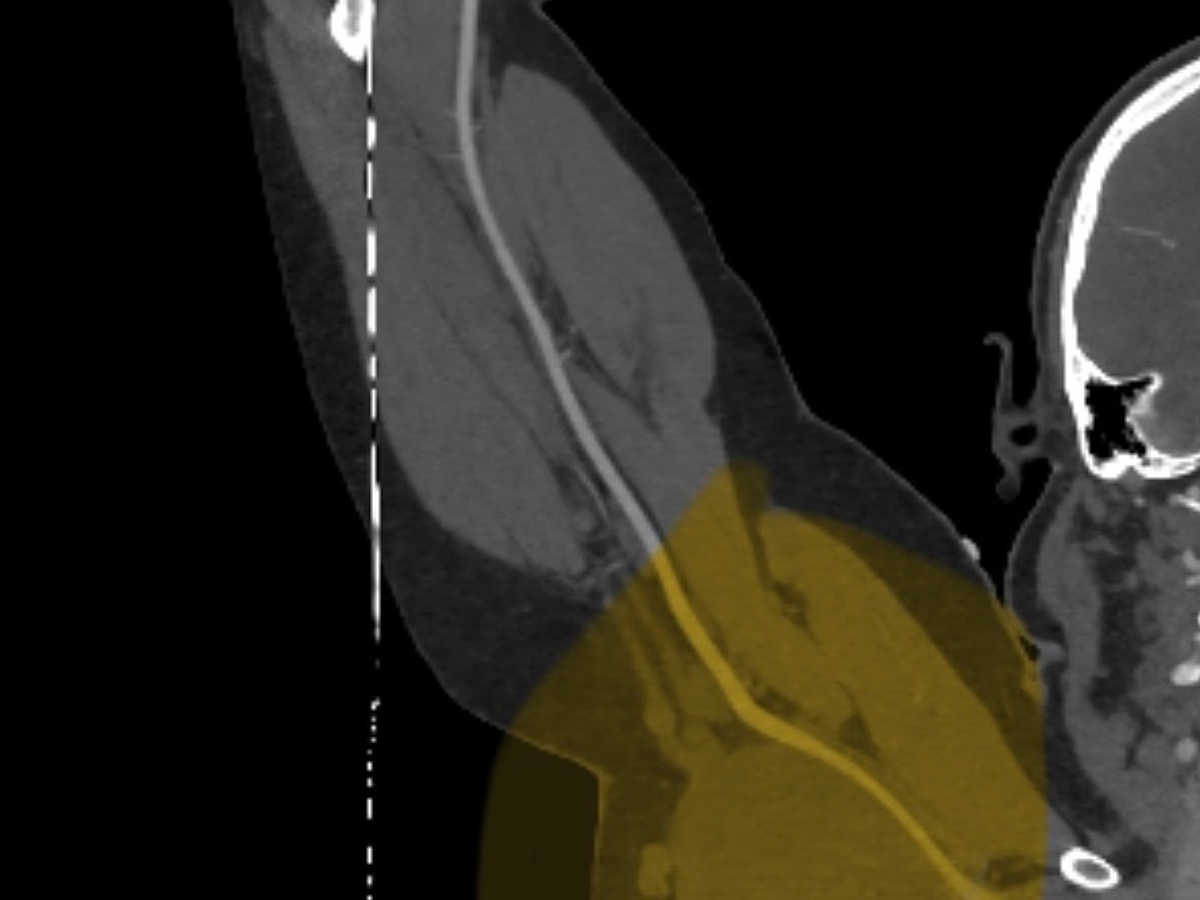

My last surgery was early last year, and recovery has gone well, but a relatively new problem has come up. In the last year or two, we discovered that a tumor in my left arm has been growing pretty aggressively and is starting to concern doctors enough that they are planning surgery. Hopefully, by the end of January or early February, this time surgery is slightly more risky than my previous ones due to the number of nerves that are running through the tumor. They are predicting about a 10% chance of losing feeling in parts of my arm and a slight chance I lose the ability to use my arm at all.